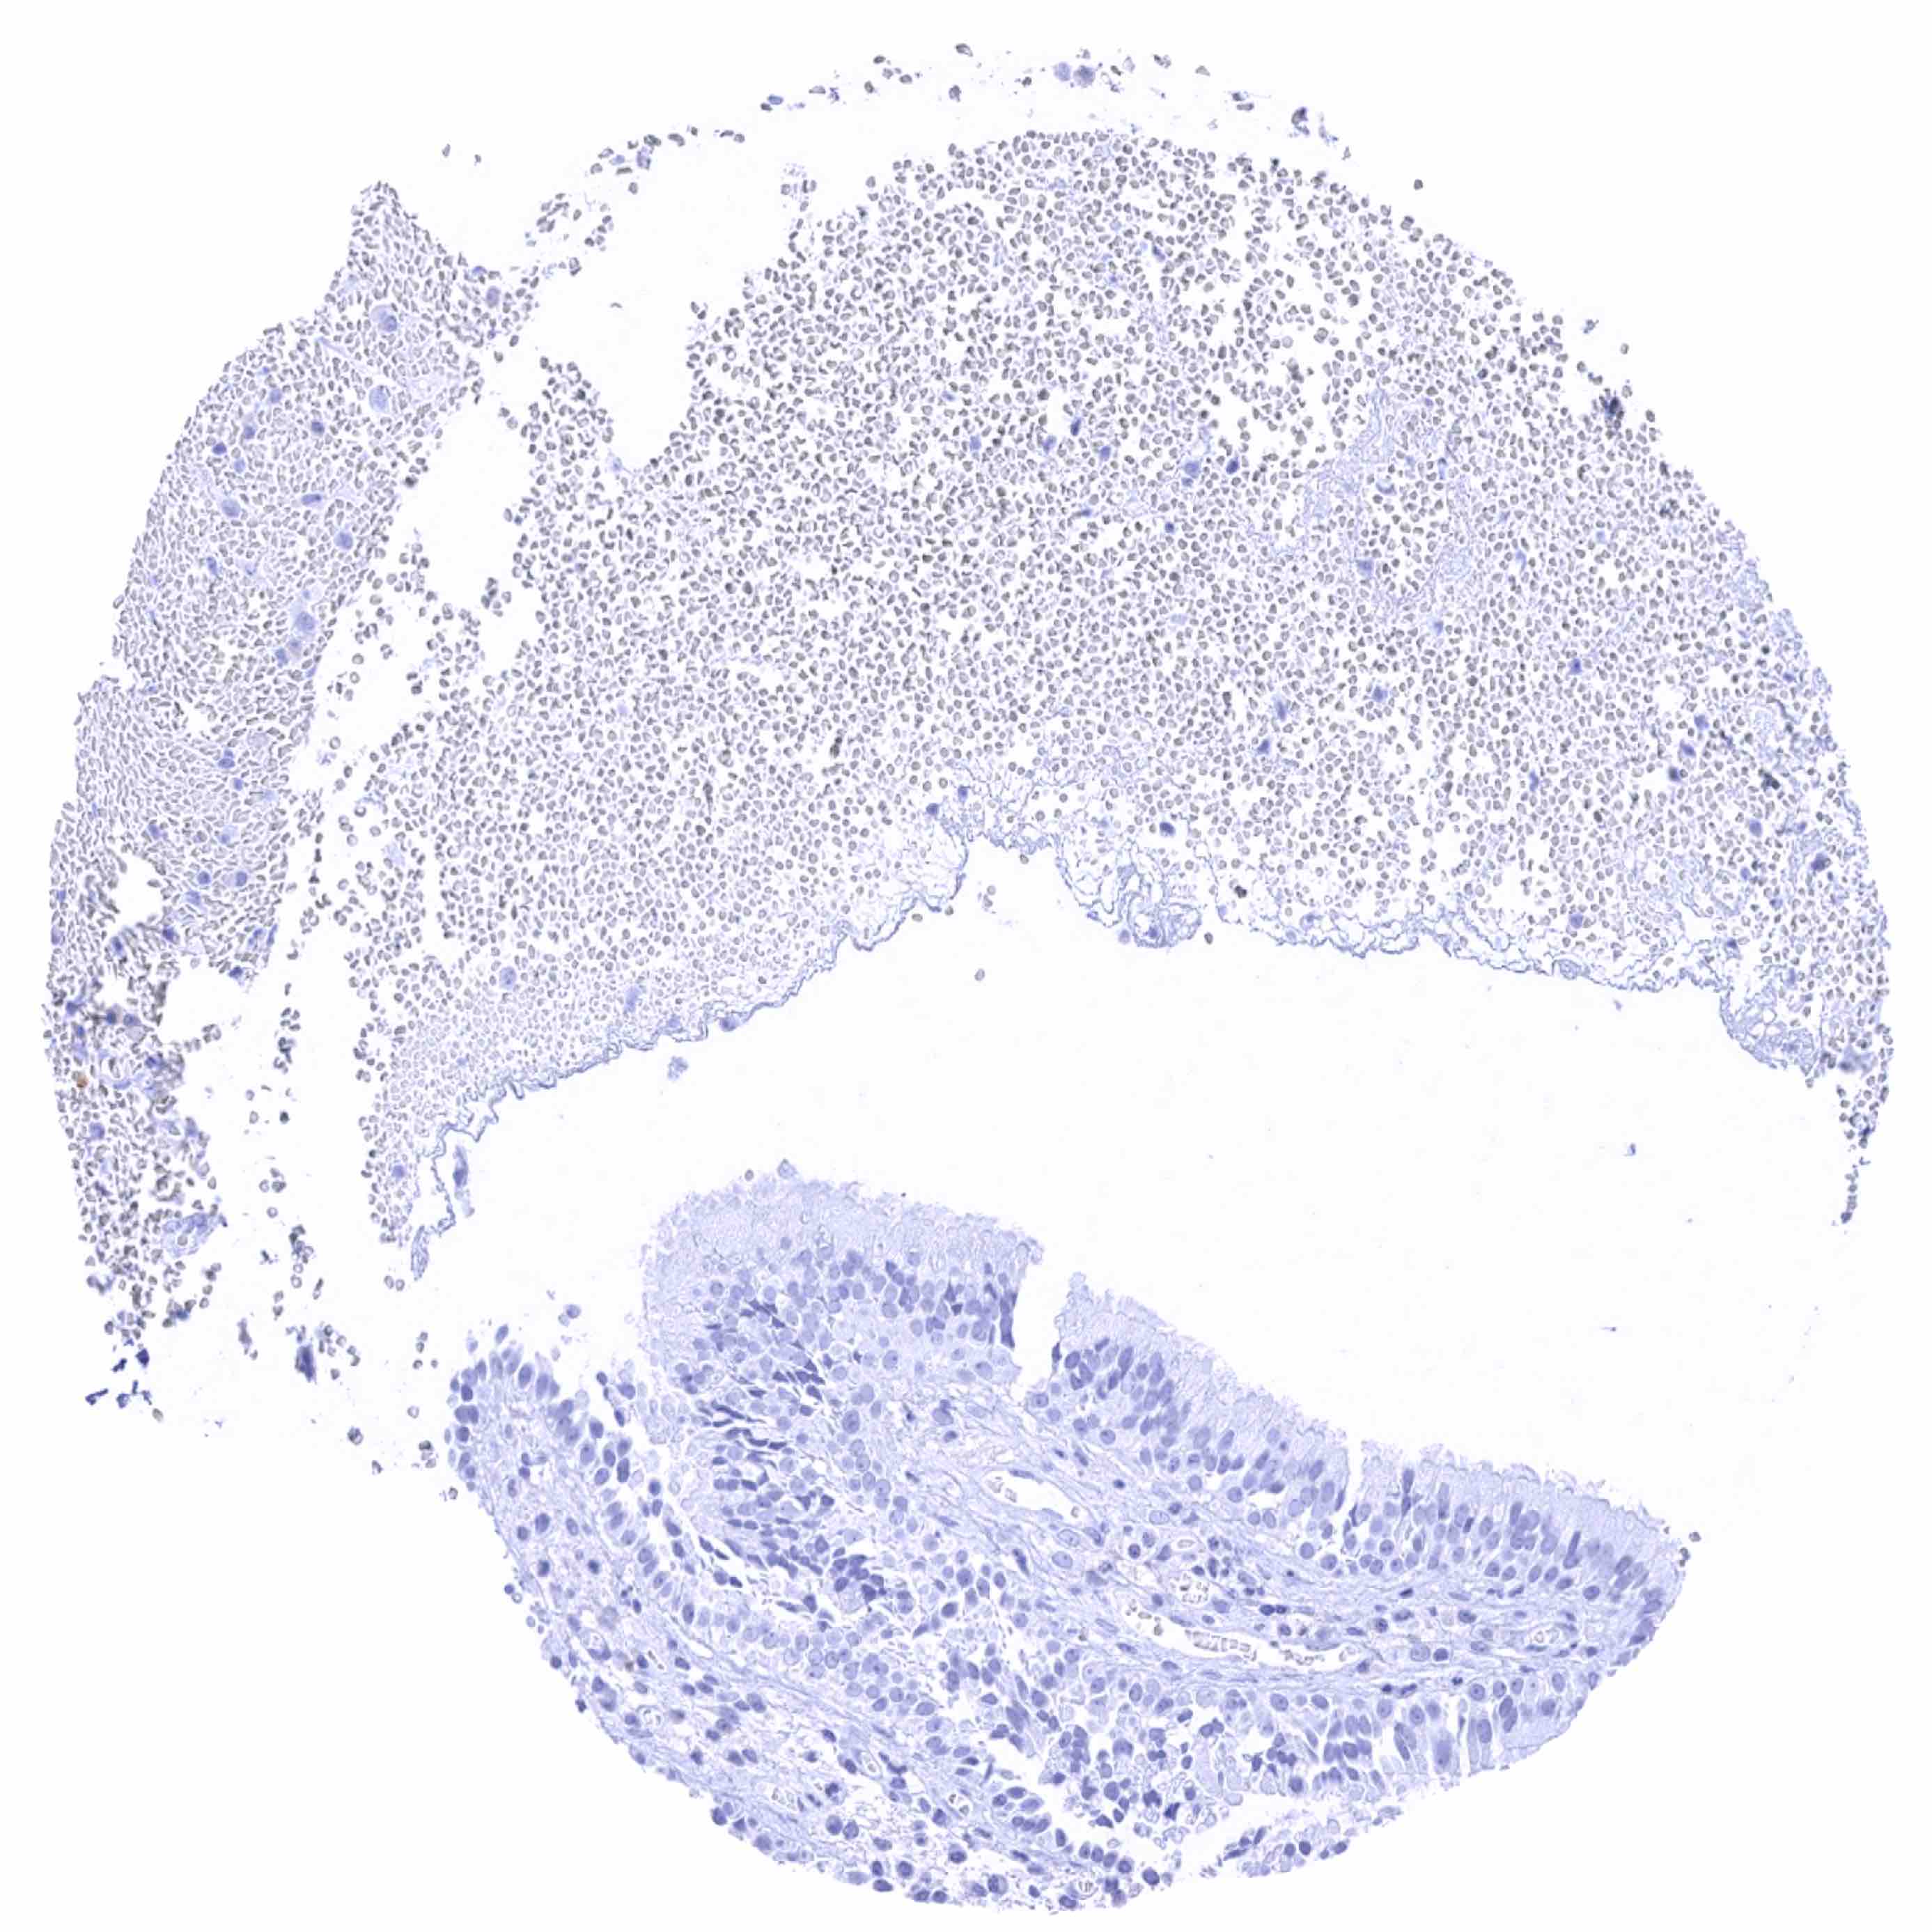

Spleen

Thymus

Tonsil